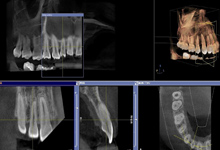

2回目にお話しした治療方針によっては歯形の採得やCT撮影などを行います。これによりさらに精密な診断を行うことができます。